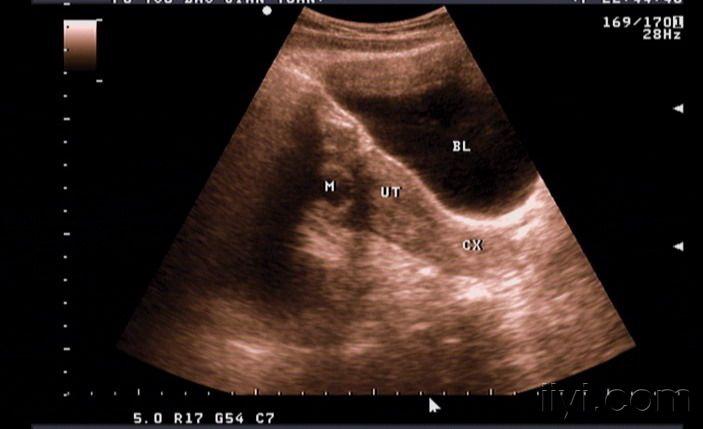

黄体血肿? - 超声医学讨论版 -丁香园论坛

图片尺寸2736x3648